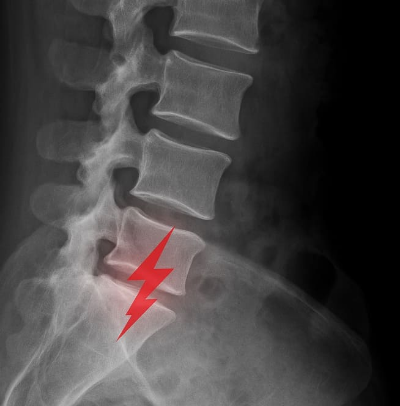

- X-ray: 척추 구조 이상 확인

- MRI: 디스크 탈출, 협착 여부 확인

- CT: 정밀한 뼈 구조 분석